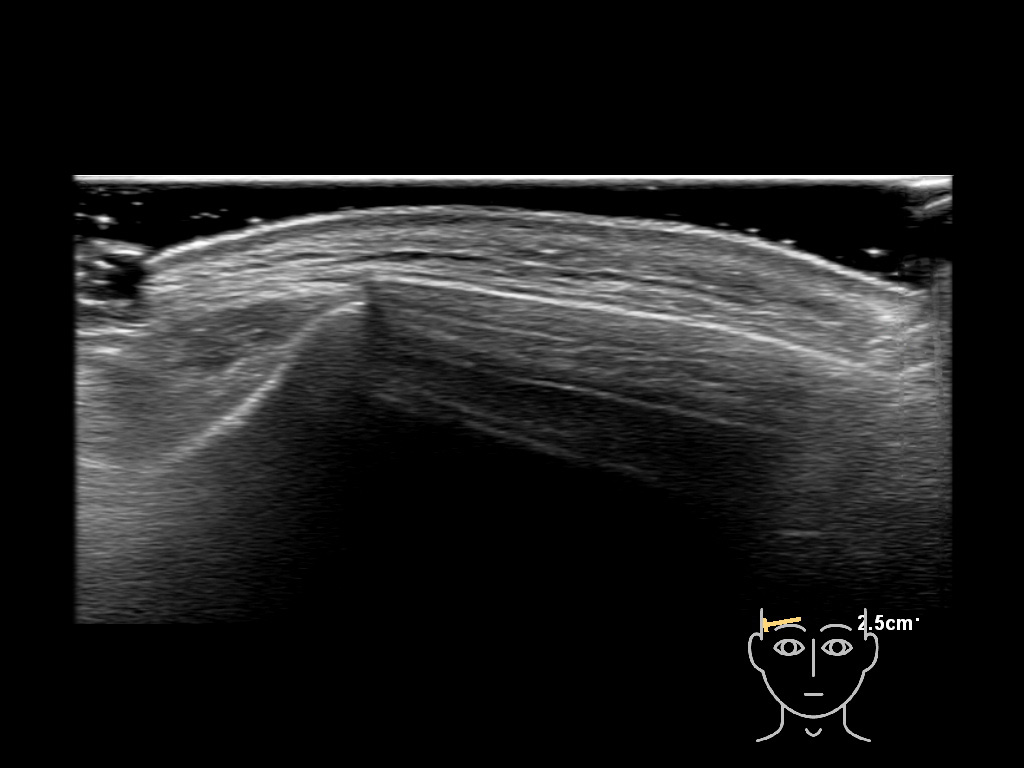

In this section you will learn more about the different layers of the face with the use of ultrasound. When you click on the secondary ultrasound image, you will see the different structures as an overlay. This will help to train yourself to recognize the different layers of the face.

Study the first image to recognize the different layers. If you are sure about the layers, swipe to the second image to view the answer (if applicable).